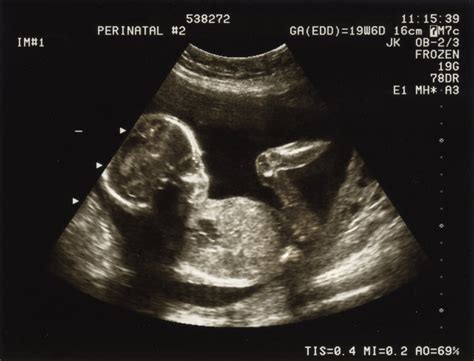

Diagnosticarea Prezentatiei Pelviene

Cu câteva săptămâni înainte de data estimată a sarcinii, medicul va palpa abdomenul mamei pentru a localiza capul, spatele și fesele copilului. Dacă există vreo suspiciune că bebelușul se află în prezentație pelviană, medicul obstetrician va efectua o ecografie pentru a confirma poziția.

Prezentația fetală descrie poziția în care se regăsește fătul în interiorul uterului matern la finalul sarcinii. Tipul de prezentație la naștere descrie ce parte a corpului bebelușului este pregătită să se angajeze prima în canalul nașterii. Felul în care este poziționat fătul poate influența dinamica travaliului, iar anumite prezentații fetale sunt contraindicate pentru nașterea pe cale naturală.

În aproximativ 95% dintre sarcini, fătul se regăsește într-o poziție craniană sau cefalică, cu capul în flexie, orientat inferior spre canalul nașterii. Aceasta este prezentația ideală pentru naștere. În prezentația transversă, fătul este orientat pe o axă orizontală de-a lungul uterului, umărul fiind segmentul anatomic cel mai apropiat de intrarea în canalul nașterii.

Medicul obstetrician va examina cu atenție abdomenul matern și va efectua manevrele Leopold pentru a stabili poziția fătului. Pentru mamele feților aflați în prezentație pelviană sau transversă, care doresc o naștere pe cale naturală, se poate efectua o manevră specială, numită versiune cefalică externă, prin care se încearcă repoziționarea fătului într-o poziție cefalică.